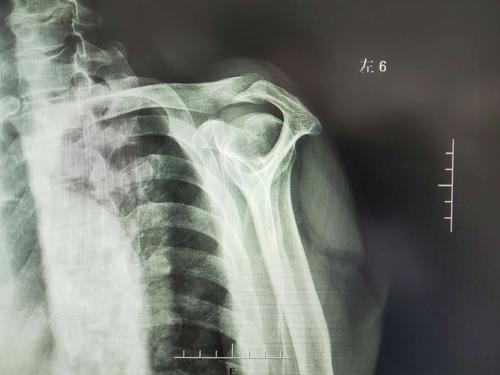

肩关节斜位片是指间关节外的一种影像学的X线检查方法,在进行斜位拍摄的时候,可以让关节倾斜30-45度,主要看肩胛骨的损伤情况。肩关节主要是由肱盂关节、肩锁关节,以及喙锁关节构成。

活动肩关节主要的大的活动范围的一个关节主要就是肱盂关节,肱盂关节就是由肱骨头和肩胛盂构成。

肩胛骨横韧带骨化:肩胛骨上的横韧带骨化(箭),使上缘与喙突间呈马鞍状,其中有小孔,不可误认为骨质侵蚀或骨囊性病变。